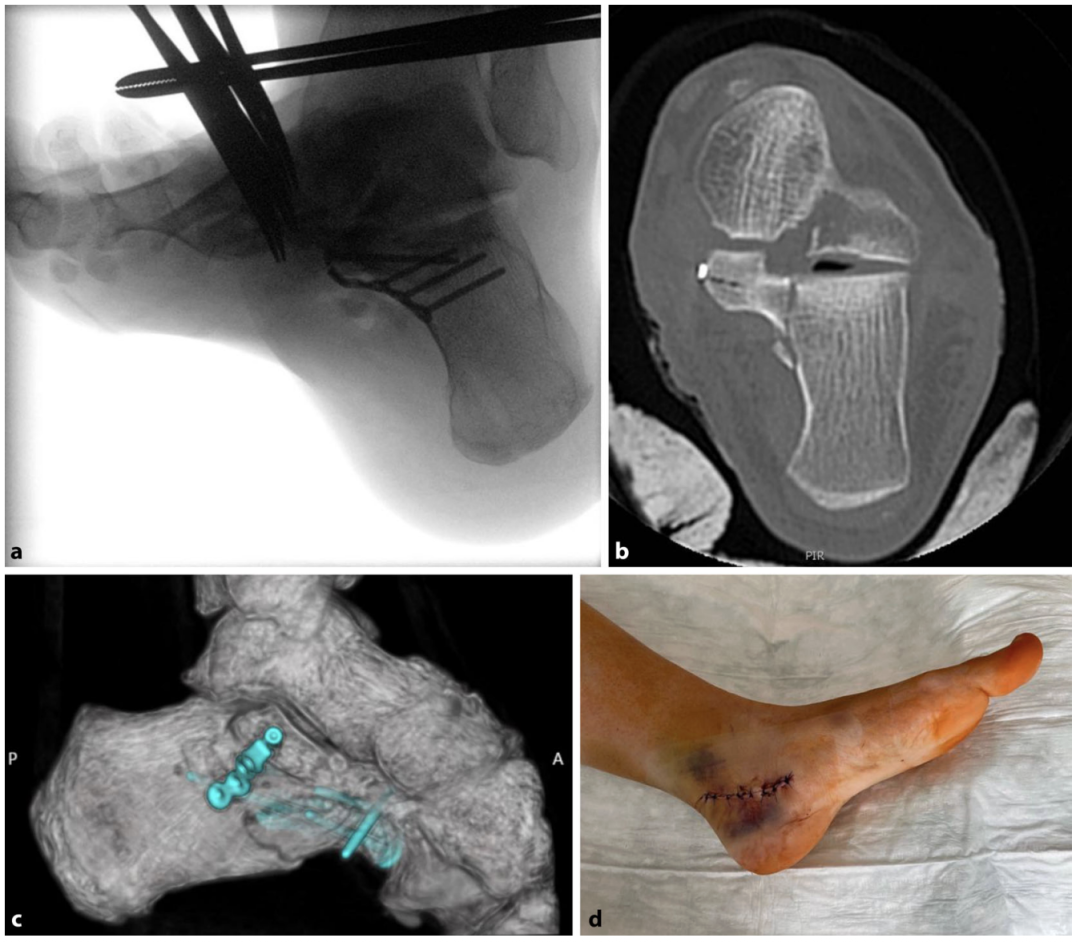

跟骨髓内钉(Calcanail:registered:):经足底入路至跟骨结节,沿向颅侧的轨迹置入距下关节面方向,距跟牵开后建立操作通道,通过该通道实现关节面的间接复位;借助牵开器,并通过操作通道(必要时可联合附加的跗骨窦入路)间接撬拨骨块,恢复后足的高度、长度与力线;通过双水平锁定的髓内钉实现骨折固定,经同一入路,还可采用更长的髓内钉假体同期行一期或二期距下关节融合术。